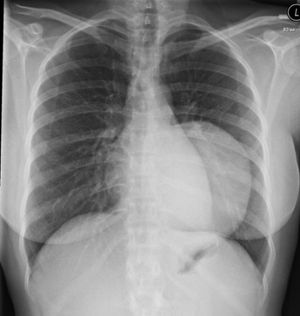

Clinical History: A 60-year-old female with pelvic fracture developed shortness of breath with tachycardia and tachypenea